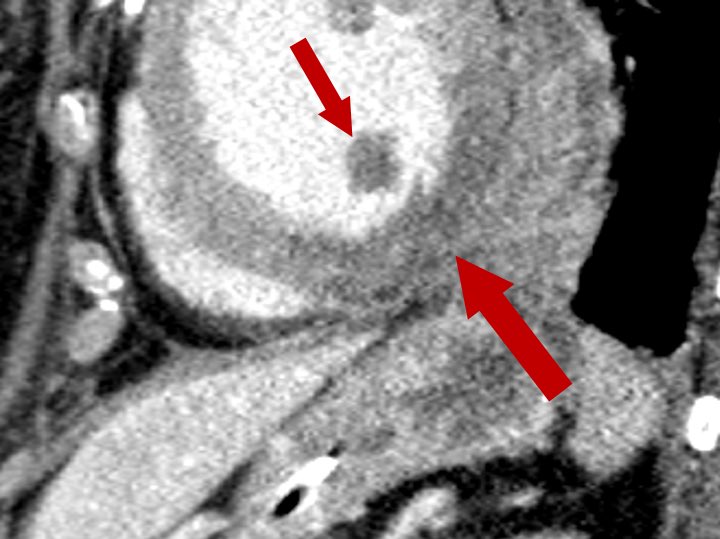

Few weeks ago I showed an acute MI on CT during lecture. Said they would probably not see this again depending on where they go Well you know how that goes, shortly after this pops up!!🫠 STEMI ➡️ Low attenuation (lack of perfusion) of the inferolateral LV wall and papillary mm

Few weeks ago I showed an acute MI on CT during lecture. Said they would probably not see this again depending on where they go

Well you know how that goes, shortly after this pops up!!🫠

STEMI ➡️ Low attenuation (lack of perfusion) of the inferolateral LV wall and papillary mm